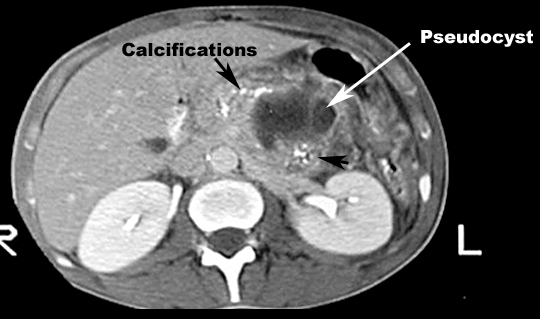

What are the anticipated imaging findings of acute pancreatitis in CT?

Contrast-enhanced CT of the pancreas is diagnostic and can show:- Enlargement of pancreas due to edema. Normal pancreas is about the same width as abdominal aorta. Abdominal aorta is 2.5 cm's in diameter. If the pancreas is larger than abdominal aorta, it is large. Normal pancreas, liver and spleen have similar enhancement with contrast. If pancreas is edematous it will be less dense compared to liver and spleen with IV contrast.

- Necrosis: On contrast enhanced phases the necrotic pancreatic parenchyma will show decreased or no enhancement when compared with normally enhancing viable tissue

- Fluid collections: A simple peripancreatic fluid collection will not have a well-defined capsule

- Pseudo cysts: As liquefaction of necrotic pancreatic tissue progresses it will gradually take on the appearance of localized fluid collection...pseudo cyst